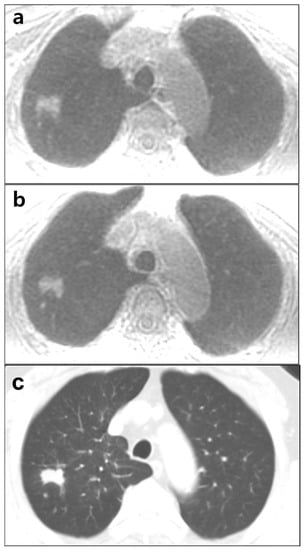

3.3. Lesion Detection